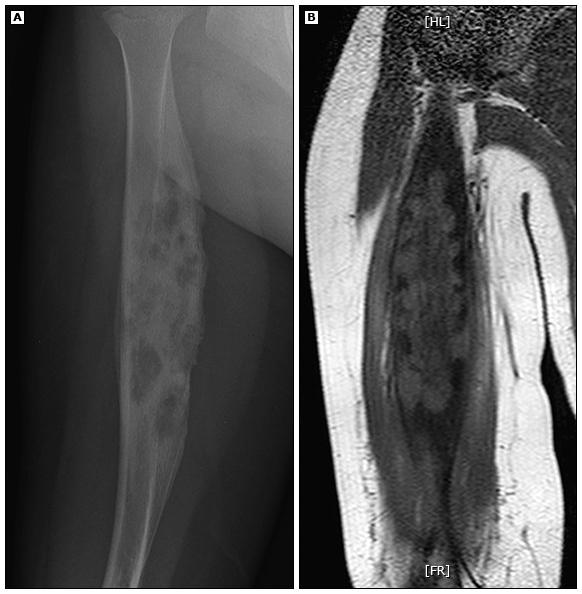

SAPHO 综合征是一种少见疾病。它是根据如下单词的首字母组合而命名: synovitis:滑膜炎 acne:痤疮 pustulosis:脓疱病 hyperostosis:骨质增生 osteitis:骨炎 该综合征最早是由 Chamot AM, Benhamou CL 在 1987、1988 年发表的系列病例讨论所描述。 在过去还曾有:胸骨锁骨骨质增生,痤疮相关脊柱关节病,脓疱性骨关节炎等命名。而 SAPHO 能相对直观且全面反映疾病特征而成为主流命名。 病理与流行病学 现在对 SAPHO 综合征的病因仍不够清楚。目前明了的有: 特定基因背景人群易罹患, 痤疮角质杆菌等感染可能参与发病 SAPHO 综合征是多因素下最终引发了炎症通路异常的疾病。 根据发病机制,慢性炎症性关节病在大体上可以分为两个大类: 跟 B 细胞产生自身抗体相关的类风湿关节炎 无抗体的自身炎症异常疾病,即脊柱关节炎 脊柱关节炎是一个谱系性疾病组合。除无自身抗体,它还有大关节、中轴关节受累;受累关节整体不对称等特征。 SAPHO 综合征是罕见病。在高加索人群里的患病率约为万分之一;但非洲裔、亚裔人(包括中国人)也有报道。由于我们没有做流行病学调研,所以中国人群的患病率是不清楚的。 该病罕见,但好发年龄段并非儿童。国外的研究证实,30 岁~50 岁是好发年龄。但 30 岁以下,50 岁以上并不少见。相对男性,女性更易罹患,这点在 30 岁以下人群更突出。 女性相对易患,尤其是 30 岁前 临床特征 SAPHO 综合征的核心要点是骨关节表现。超 60% 的病人会有皮肤改变,不少病人同时还有其他改变。 骨关节表现 骨关节病变往往累及 中轴关节:骶髂关节、脊柱关节、前胸壁 外周关节:髋关节、膝关节、踝关节 中轴关节是主要的;65%~90% 有前胸壁受累,尤其是胸骨、胸锁关节以及肋锁关节。这被认为是 SAPHO 的特征性表现之一。 不到 30% 有外周大关节受累,下肢比上肢常见。 其表现形式有骨骼、关节的疼痛、肿胀、压痛是特征。往往是多个部位,慢性或反复出现。 滑膜炎:通常为非侵蚀性的 骨炎:骨皮质、骨髓腔的炎症、水肿等 骨质增生:疾病进展后出现骨小梁、骨皮质增生,骨髓腔狭窄等,可伴骨溶解现象 医生查体时可以看到相关关节皮肤软组织的红斑、肿胀;受累骨骼、关节有压痛。 骨 X 光平片检查可看到骨质增生(骨膜、皮质和骨膜增厚)、硬化性病变、骨溶解、骨膜反应、骨增殖(即伴有附着点的骨赘的形成)。不过在起病之初可能未必有典型表现。 ( A 为肱骨 X 线片;B 为冠状位 T1W MRI 图像。其显示骨质增生和骨炎,有溶解和硬化。 ) 放射性核素骨扫描可显示多个受累部位的摄取增加。当有胸锁关节受累时,在骨扫描成像上出现所谓的「牛头状」改变,这是 SAPHO 综合征的特征之一。骨扫描是最有助于快速测量整个骨骼的「典型」位置,作为更有针对性的平片检查的辅助手段。 ( A 为骨扫描的牛头状改变,B 和 C 是胸锁关节 CT 表现)诊断治疗。 临床表现 皮肤改变 SAPHO 综合征的皮肤可表现为各种形式的痤疮、嗜中性粒细胞皮肤病。虽然关节改变、皮肤改变出现的间隔时间通常不超 2 年。但,骨关节改变跟皮肤活动性病变并不平行。 SAPHO 综合征的皮肤病变有: 掌跖脓疱病 脓疱性银屑病 Sneddon-Wilinson 病(角层下脓皮病) 银屑病 毛囊闭锁三联征:聚合性痤疮、化脓性汗腺炎 爆发性痤疮 线状 IgA 大疱性皮病 白塞病 Sweet 综合征 坏疽性脓皮病 从命名上可知,脓疱病和痤疮改变最常见。比如 60% 的皮肤改变者有掌跖脓疱病。 掌跖脓疱病,表现为手掌多发性无菌性脓疱混合黄棕色斑点 胸部皮肤受累的结节痤疮 好发于腋窝等的聚合性痤疮 其他系统表现 除骨骼关节病变、皮肤病变外,SAPHO 综合征还有其他脏器表现: 静脉血栓形成,最常影响锁骨下静脉 肥厚性厚膜脑膜炎 眼葡萄膜炎 坐骨神经痛(可能是由于软组织受累和侵犯脊髓神经所致) AA 淀粉样变性伴相关肾损害 胸膜异常,包括实质和胸膜改变 坐骨神经痛 诊断与鉴别诊断 SAPHO 综合征的诊断颇具有挑战性。一方面该病少见。另一方面是医生常常没能把关节症状与皮肤病变联系在一起。 对于有前胸壁、骶髂关节、脊柱的炎症性关节病变,并有嗜中性粒细胞皮肤病、痤疮样皮疹时都应该考虑 SAPHO 综合征可能。应再三强调,皮疹的活动性跟关节病变不平行。 正确的诊断的前提是良好的鉴别诊断。 对于骨关节病变,应跟细菌性骨髓炎、原发性骨肿瘤、朗格汉斯组织细胞增生症等鉴别。 银屑病关节炎、肠病性关节炎容易跟 SAPHO 综合征混淆。因为不少皮肤病专家认为掌跖脓疱病也属于广义上的银屑病。但也有不少皮肤病专家持否定态度。 还需要跟很多遗传性的炎症性病变鉴别: DIRA(白介素-1 受体拮抗剂缺陷):新生儿发病,类似脓疱型银屑病、熔骨性改变 DITRA (白介素-36 受体拮抗剂缺陷):儿童及成年早期发病,泛发性脓疱型银屑病改变。 CAMPS (CARD-14 介导的脓疱型拮抗剂):儿童早期,泛发性脓疱型银屑病。 ADAM17 缺失/新生儿发生的炎症性皮肤病和肠病:新生儿发病,红皮病性银屑病、泛发脓疱、甲沟炎、短发、腹泻(常血性) PAPA 综合征(化脓性关节炎、坏疽性脓皮病和痤疮):儿童发病,坏疽性脓皮病、严重痤疮、反复的无菌性关节炎 PAPA 患者的坏疽性脓皮病 治疗 对于仅有骨关节症状者,我们会首先尝试单纯的非甾体消炎药治疗。也可以尝试联合柳氮磺吡啶、秋水仙碱治疗。但是,对重症病人还是应联合抗 TNF-a 制剂、甲氨蝶呤。 对于有广泛性掌跖脓疱病的 SAPHO 综合征病人,我们首先口服阿维 a 酸治疗。 对于有中重度痤疮的 SAPHO 患者,应联合四环素、异维 A 酸治疗。异维 A 酸不仅仅可以改善皮肤,也可以改善骨关节病变。 对于初始治疗反应不佳,可以考虑抗白介素-1 制剂、抗白介素 12/23、抗白介素 17 制剂、双磷酸盐。